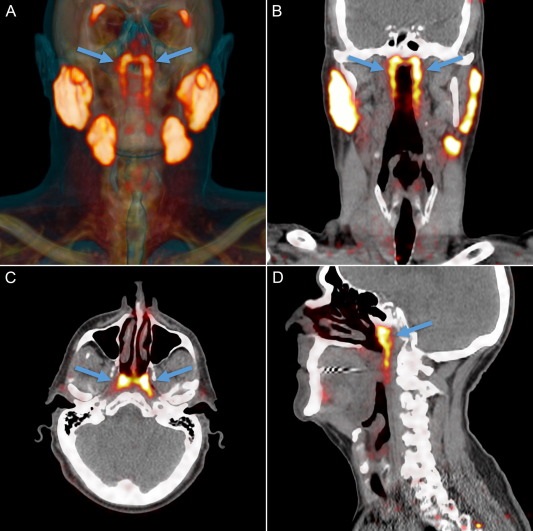

Медики обнаружили в организме человека четвертую пару крупных слюнных желез - органа, о существовании которого ранее никто не подозревал. Ученые назвали эти железы tubarial (трубными). Они находятся почти в геометрическом центре черепа, ближе к его основанию. Вероятно, из-за такого расположения железы до сих пор оставались незамеченными. Любопытно, что это первое подобное открытие за последние 300 лет пишет Radiotherapy and Oncology.

Исследователи для обнаружения и визуализации опухоли в организме взяли меченую радиоактивными изотопами глюкозу. Специалисты обнаружили, что глюкозу поглощали не только опухоли, но и некие органы, которые и оказались четвертой парой слюнных желез.

Как выяснили медики, четвертая пара слюнных желез отвечает за смазку и защиту носоглотки и зева.